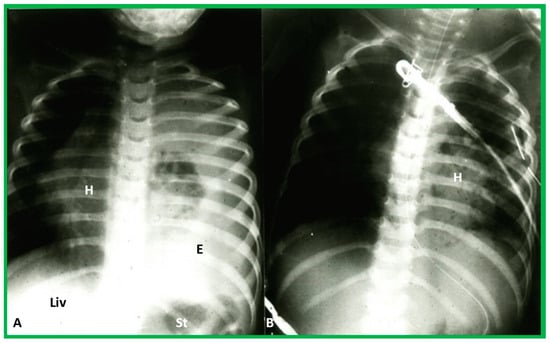

Figure 12. Chest X-rays of a five-year-old patient who was seen for evaluation since the referring physician noted a right-sided heart. Physical examination was unremarkable. (A) The heart (H) is displaced to the right, and there was no obvious pulmonary pathology. The gaseous shadow of the stomach (St) is located on the left side (normal). (B) The sternum (arrow) is showing posterior displacement, presumably causing dextroposition of the heart. Modified from reference [3].

Figure 13. (A) Chest X-ray of a child with left-sided empyema (E), displacing the heart (H) to the right side. The liver (Liv) and stomach bubble (St) are in a normal position, indicating no evidence of situs abnormality. (B) Following drainage of empyema, the H is moved back into the left side of the chest. Modified from reference [3].